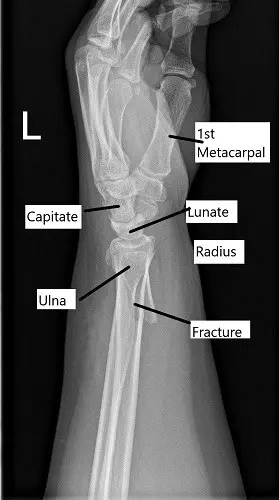

The x-ray of the left wrist revealed an oblique fracture of the distal left radius which communicates with the articular surface. There is a nondisplaced fracture of the distal left ulna. Further radiological studies in the form of CT scan revealed rotation of the distal fragment, with approximately 24 degrees of resulting apex-volar angulation.

X-ray showing distal radius fracture in lateral view.